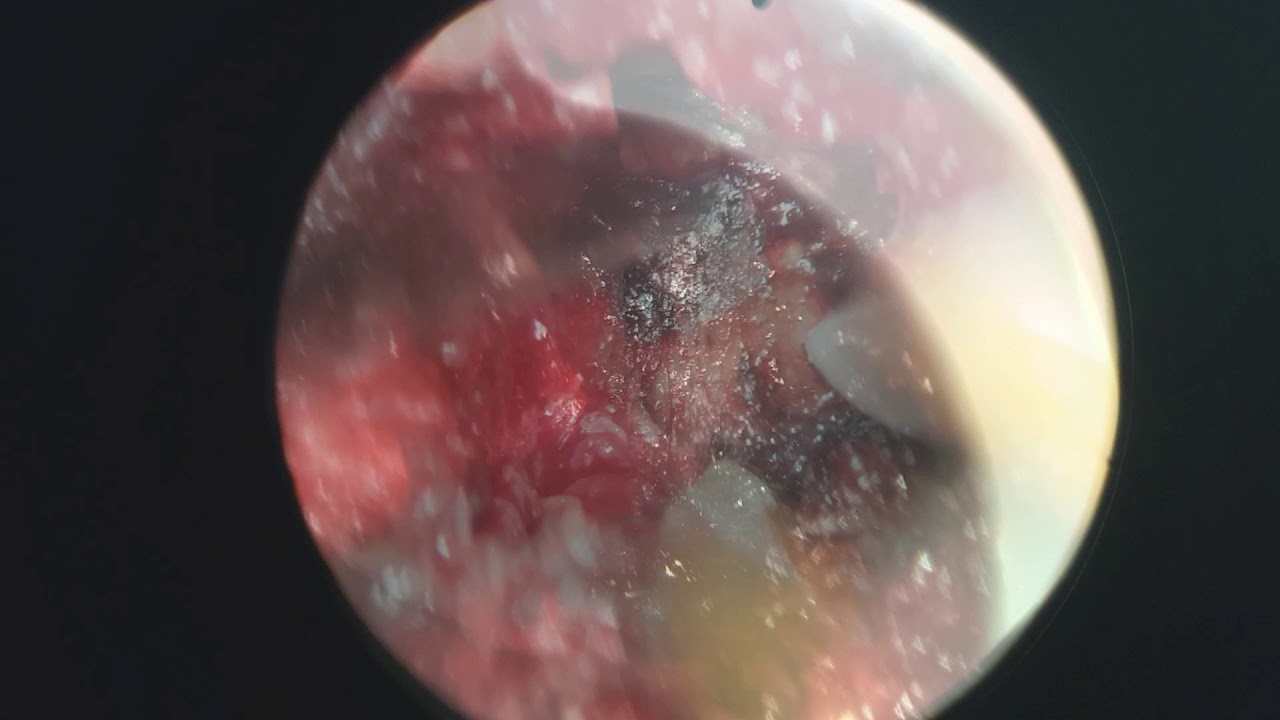

- Neuroendoscopia

Fotos y videos